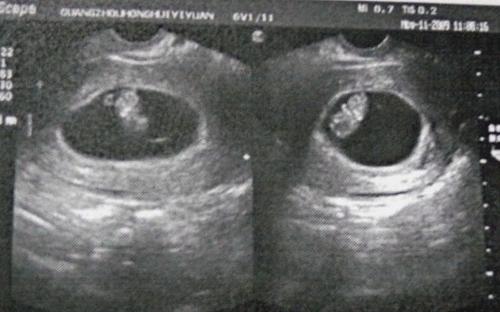

2.孕囊形状及数据。看怀孕40天左右的B超单上孕囊的形状和数据。一般认为圆形孕囊为女孩,茄子形孕囊为男孩。但是由于B超师截取的方位不同,依据孕囊大小的三个数据更为准确。如果成等差数列,例如40*30*20,为女孩;如果两个数据相似,且为第三个数据的一倍,例如40*40*20,则为男孩。

豆妈孕囊大小为20*30*17。